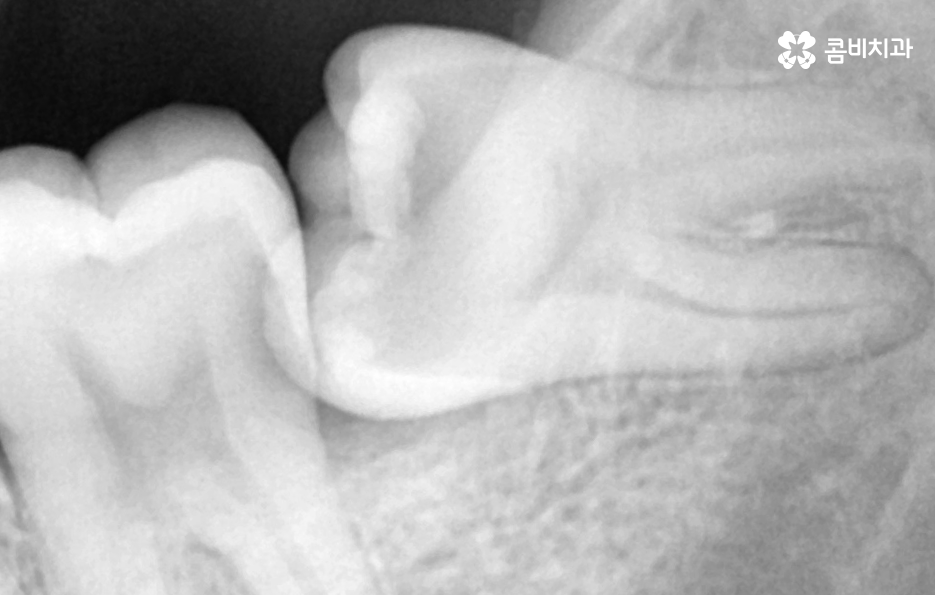

부분매복 사랑니 발치 두 번째 문제는 옆 어금니의 충치와 뼈 손상으로 부분매복 사랑니가 비스듬하게 누운 형태로 자라는 경우가 많은데, 이때 사랑니가 바로 앞 어금니 2번 치아(제2대구치)의 뿌리를 밀어내거나 치아 사이에 음식물이 지속적으로 끼게 될 수 있었어요

이 사이에 끼는 음식물은 아무리 칫솔질을 해도 제거가 어렵기 때문에 앞 어금니가 충치에 취약해지며 실제로 사랑니 때문에 앞 어금니가 충치가 생기고, 결국 큰 신경치료까지 가는 사례가 많은데 더 심하면 앞 어금니 뿌리 주변 뼈가 녹아 앞 치아까지 흔들리는 상태가 되기도 해서 사랑니 자체보다 옆 치아가 더 큰 피해를 보는 경우가 많다는 점이 부분매복 사랑니의 큰 문제점이라 할 수 있어요